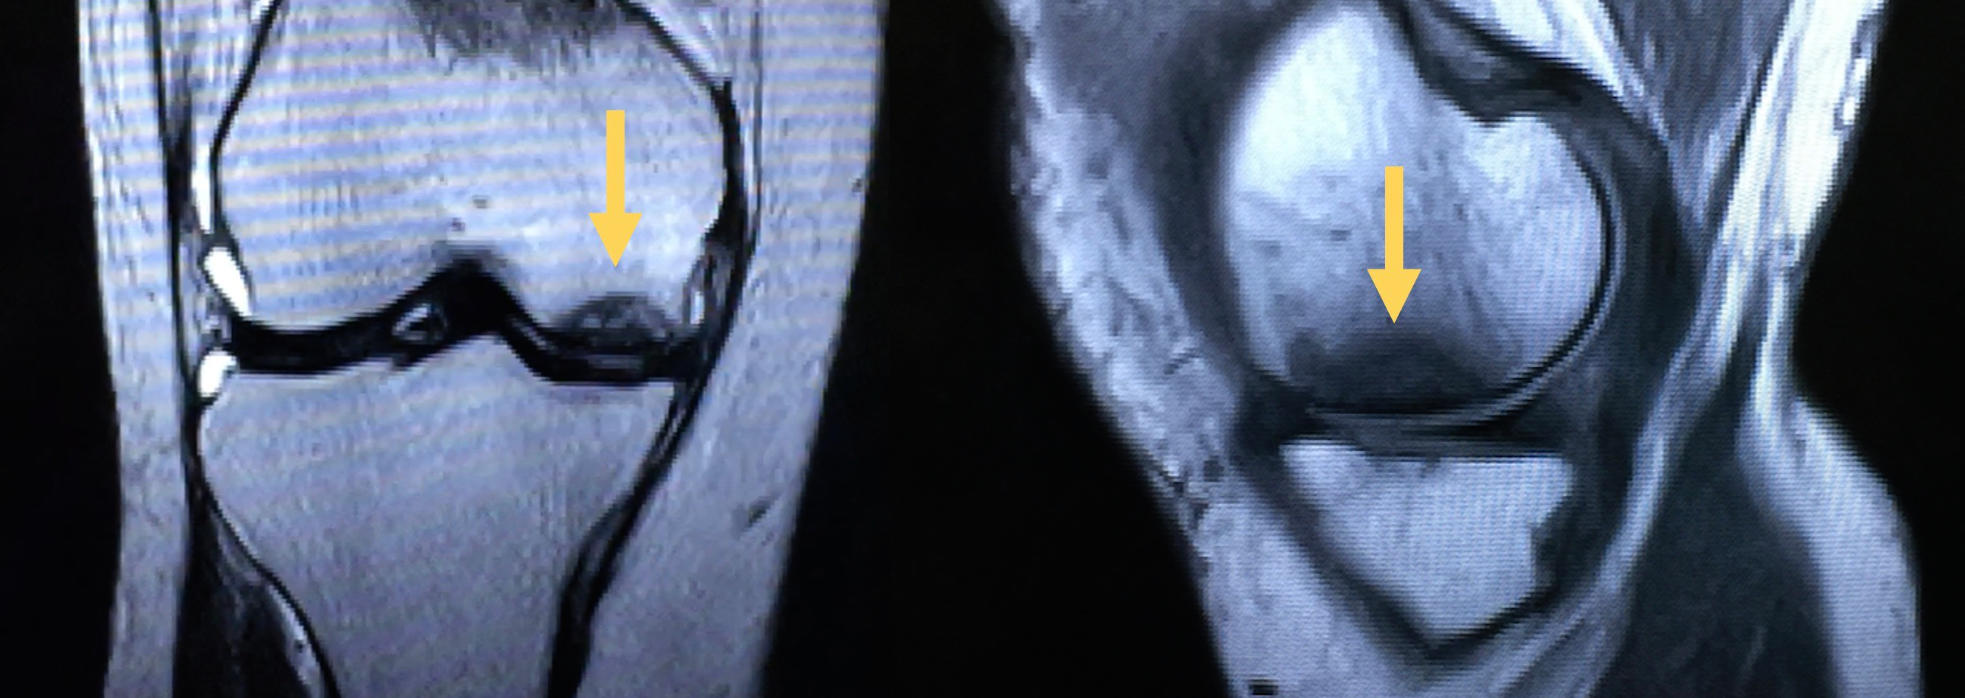

In the early stages the condition is not seen on x-ray but can be seen with MRI. In these early phases, there are some potential non-joint replacement options that attempt to stop the progression of the process. As the osteonecrosis process worsens, the cartilage surfaces can collapse into the dead bone area causing more significant pain and disability. Once the process goes on to joint surface collapse, joint replacement is the only solution to relieve the pain and restore function.

MRI View